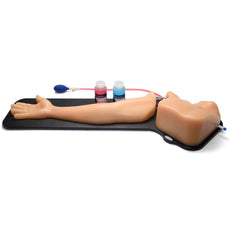

Replacement tissue insert for Central Line and Regional Anesthesia Model (BPHNB670 series).-

Includes:

- 1 bottle of Red Ultrasound Refill Solution, 235 mLs

- 1 bottle of Blue Ultrasound Refill Solution, 235 mLs